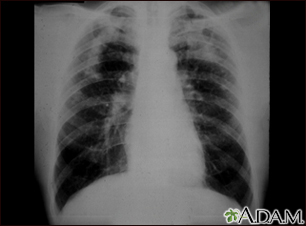

Coal workers pneumoconiosis, complicatedBackCoal workers pneumoconiosis, complicatedThis picture shows complicated coal workers pneumoconiosis. There are diffuse, small, light areas (3 to 5 mm) in all areas on both sides of the lungs. There are large light areas which run together with poorly defined borders in the upper areas on both sides of the lungs. Diseases which may explain these X-ray findings include complicated coal workers pneumoconiosis (CWP), silico-tuberculosis, disseminated tuberculosis, metastatic lung cancer, and other diffuse infiltrative pulmonary diseases. E-mail FormEmail ResultsName:Email address:Recipients Name:Recipients address:Message: